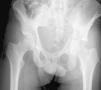

Patients met with some of the factors defined as poor prognosis for open reduction and internal fixation: communition, severe impaction or erosion of the joint surface, gull sign (Fig. 1), and associated fracture of the femoral head or neck.3

Mean patient follow-up was 40 months, with a range of 20–130 months. The final mean HHS was 96.2 (with a SD of 4.3) (Fig. 1) and Merle D’Aubigné score as “excellent” for 93% of the patients. Both results may be marked within the range of excellent regarding functional recovery of patients, who often went back to the activities of their lives prior to the fracture. Lastly, only 2 patients required assistance in walking outside the home, one with sticks and another with a walker (more due to apprehension of fearing a second fall).